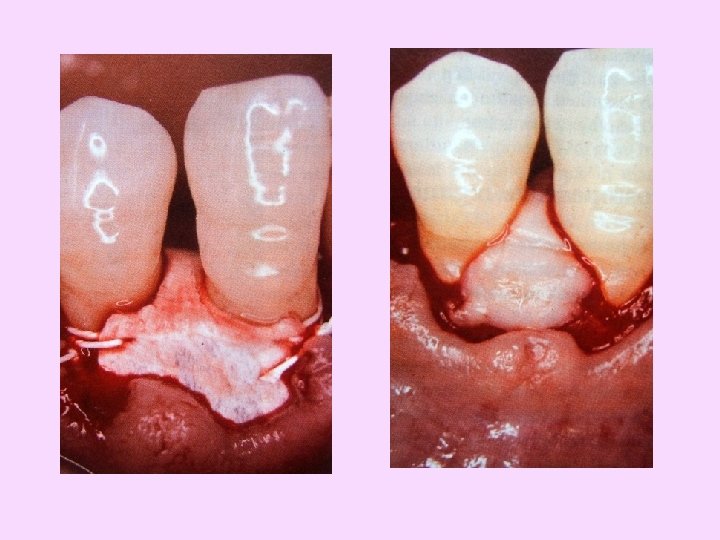

Procedure Preparation of trapezoidal flap

Preparation of trapezoidal flap

Flap reflection De-epithelization

Debridement Root concavity

Membrane stabilization